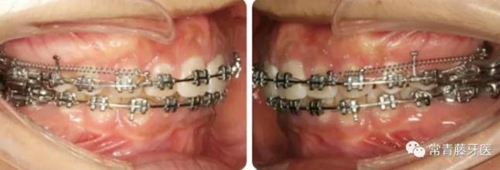

A67、B67之間植入微種植釘整體內(nèi)收上牙列,下頜配合多用途弓整平牙列改善覆合。

繼續(xù)內(nèi)收上牙列,此時(shí)下頜spee曲線基本整平。